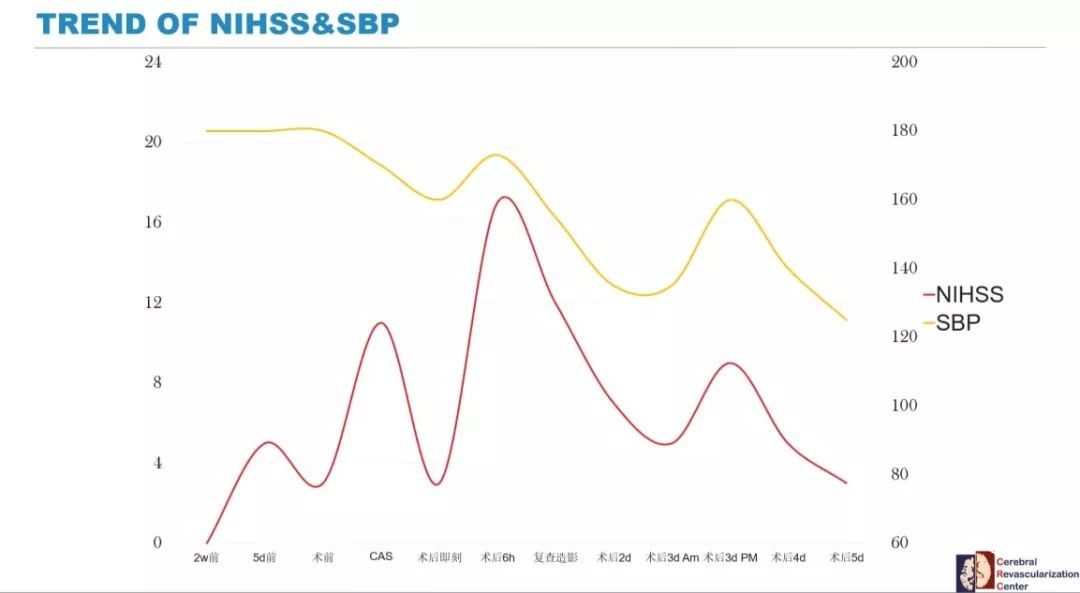

随着患者转出监护室,回到普通病房后第二天病情的再次波动,提示患者颈动脉血管成形支架植入术后的神经功能缺损反复出现是脑过度灌注综合征的表现。严格控制血压在120mmHg,患者术后第5天,NIHSS 3分,完全恢复至术前情况。总结一下患者的病情变化曲线与血压的波动:

那么该患者究竟是“高灌注综合征”的一元论,还是“祸不单行”,手术即刻是栓塞事件,随即出现造影剂脑病,术后6小时出现高灌注综合征?最终的结论,有待于当时补充更多的证据,这也或许永远是个谜。